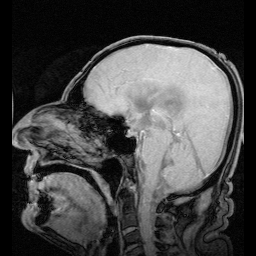

什麼是頭薦骨系統?

由中樞神經系統、腦脊髓液、容納腦脊髓液的腦膜,以及和這些腦膜相連的骨頭構成的系統,就是從頭骨到脊椎延伸至尾椎的系統。

美國骨科醫生威廉‧嘉納‧蘇德蘭在二十世紀初工作時的發現。經過多年臨床經驗後,頭薦骨療法的先驅們發現其實骨頭不是問題的核心,真正發揮影響力的是頭薦骨系統中的薄膜組織,例如分佈在腦中的大腦鐮和小腦幕,它們不僅牽動頭骨的活動,也透過脊椎和遍布人體的薄膜系統影響到全身。然而再度經過多年的臨床經驗,他們又發現原來薄膜組織也不是核心,一切的根源在於體液的流動,例如充斥頭薦骨系統中的「腦脊髓液」,而這些體液的流動根源自人體的「原生呼吸」。